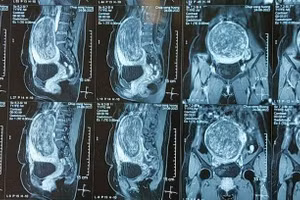

GD&TĐ - Nữ bệnh nhân 49 tuổi ở Tuyên Quang phát hiện khối u xơ tử cung nhưng quyết định tự dùng thuốc nam để điều trị. Sau đó, khối u phát triển rất nhanh, chiếm hết toàn bộ tử cung của người phụ nữ này.

GD&TĐ - Các bác sĩ Bệnh viện Phụ sản Thành phố Cần Thơ vừa phẫu thuật thành công cho một bệnh nhân mang khối u có kích thước “khổng lồ” với đường kính 30cm, nặng đến 6kg.